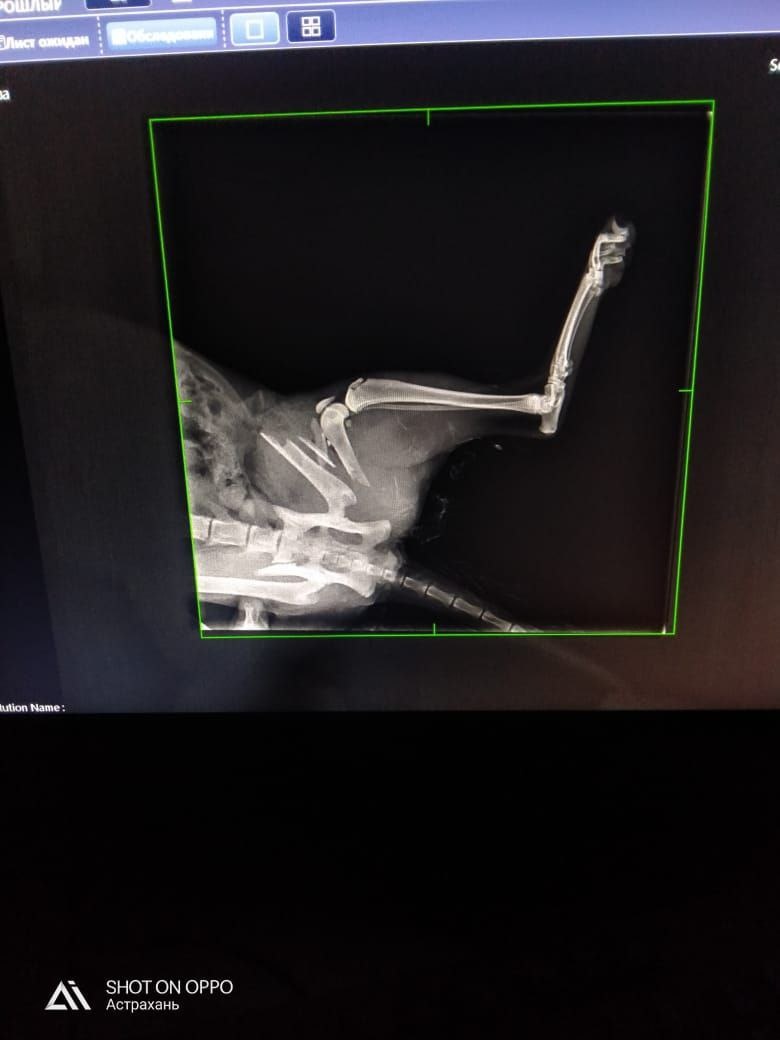

Просим оказать помощь в сборе средств на лечение молоденькой кошечки, которую погрыз домашний соседский пес.

Требуется операция на лапу, уже затрачено 17 100.